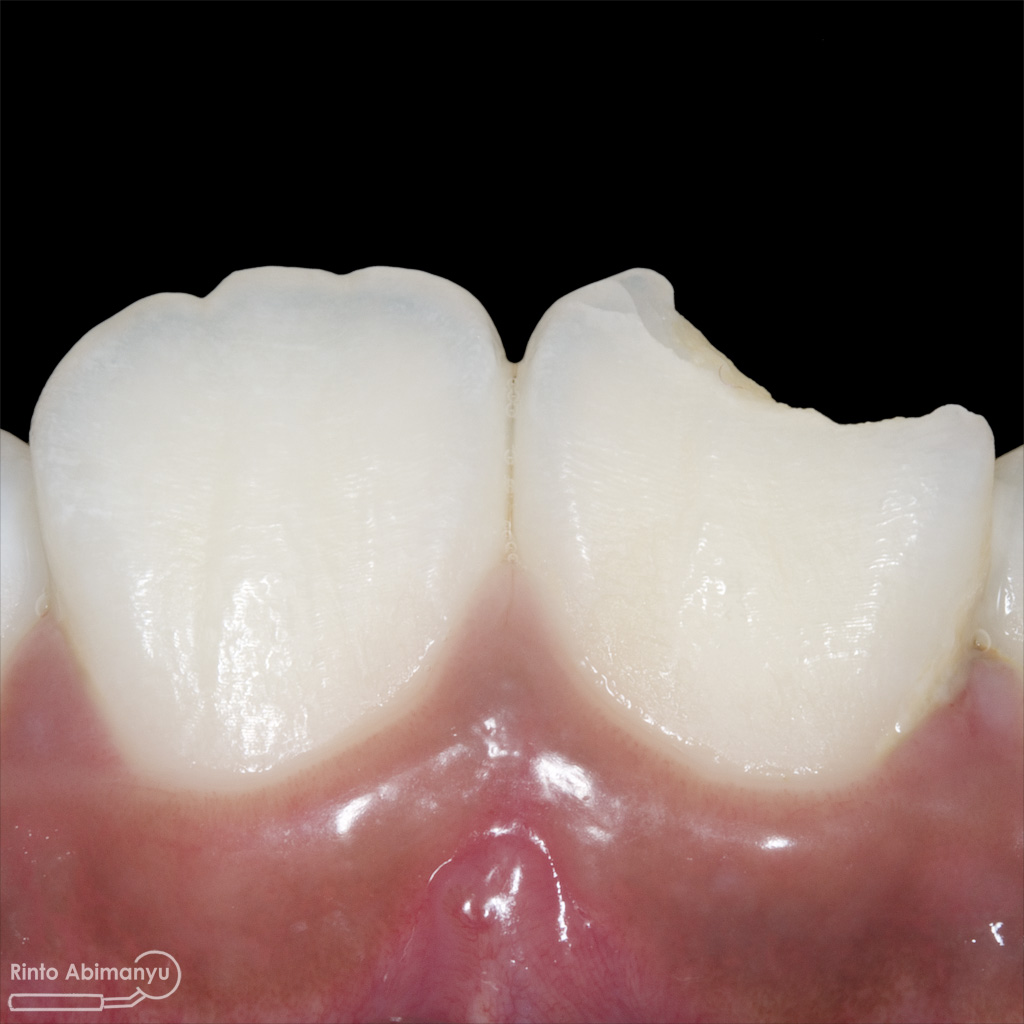

Pada pemeriksaan intra oral terlihat gigi 23 dan 24 mengalami karies dan cukup banyak sisa makanan terjebak disana…

Pemeriksaan respon dingin pun menunjukkan hasil negatif, untuk menambah data dalam penegakan diagnosis maka dilakukan pengambilan ronsen pada gigi2 tersebut